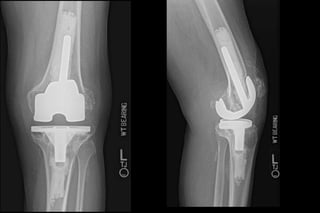

68 yo male

6 weeks postop

Total Joint Arthroplasty •Widely successful • Rapid improvement in pain/function (90%) • Durable